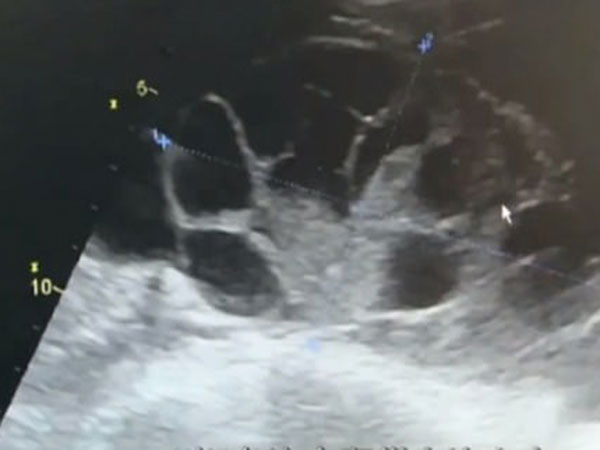

The woman was diagnosed with ‘ovarian hyperstimulation syndrome.' This is a condition that happens when ovaries become too stimulated for egg growth and fluid builds up around them.

The doctors revealed that more than five litres of fluid had been drained from her abdomen. Apparently, her ovaries had expanded as if she had been pregnant for 7-8 months!